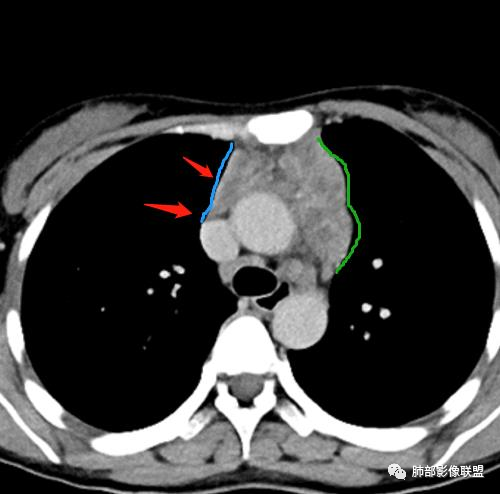

2.影像显示前纵隔不规则块状影,依势贴附心脏大血管旁,密度不均,边界不甚清楚,有结节融合感。

3.病灶轻度不均匀强化,可见血管穿行,散在液性低密度区。

双肺门未见肿大淋巴结。

4.双侧腋窝区见增大淋巴结,边界清楚。